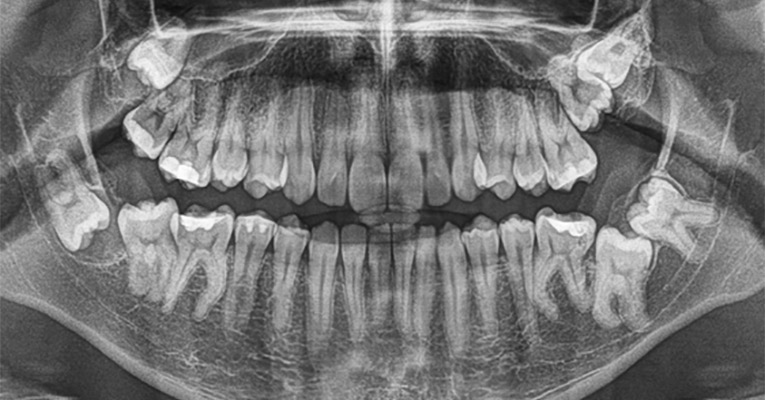

To jeden z najczęstszych ale bywa, że najtrudniejszych zabiegów z zakresu chirurgii dentystycznej. Zaklinowane, tudzież zatrzymane zęby widoczne są dopiero po wykonaniu zdjęć panoramicznych szczęki (tak zwanego pantomogramu). Na ich podstawie doświadczony chirurg stomatolog jest w stanie zapewnić najlepsze, a zarazem najmniej inwazyjne rozwiązanie problemu. Usunięcie tak zwanych zębów mądrości czasami związane jest z interwencją chirurgiczną w obrębie kości – to rzadki przypadek, wymagający sporego doświadczenia chirurgicznego. Po usunięciu zęba oczyszcza się dokładnie powstałą na skutek ekstrakcji ranę i zabezpiecza przez niepożądanymi czynnikami.